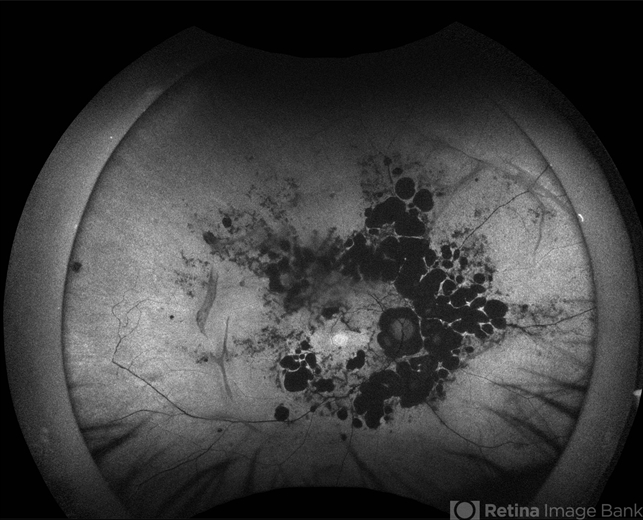

California ICG OPTOS - Description

- Fundus Autofluorescence of an 46 YO female patient diagnosed with Idiopathic Multifocal Choroiditis. Findings were bilateral.